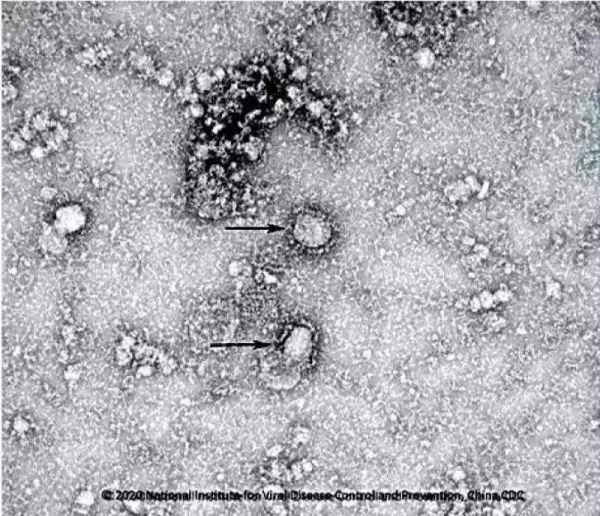

△中国疾控中心已成功分离我国首株新型冠状病毒毒种